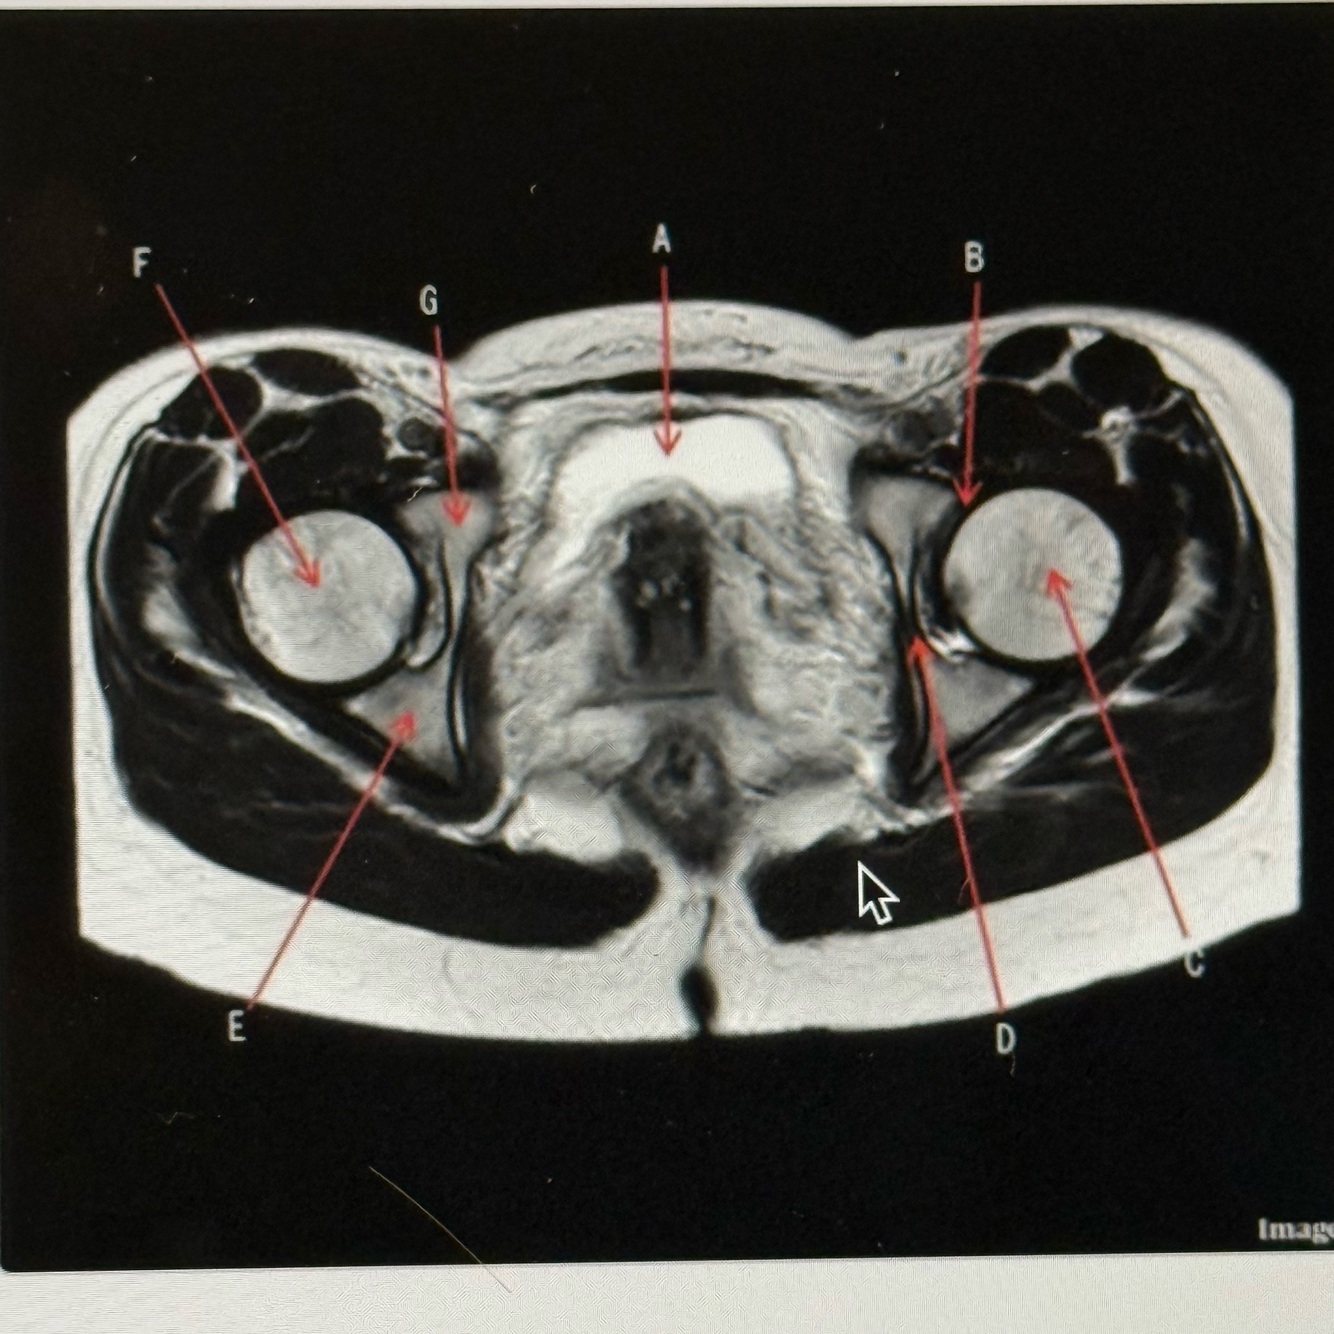

The image below is a ______ weighted image acquired in the _____ scan plane.

A

T2; Axial

5

Q

Letter A is pointing to the

Bladder

6

Letter B is pointing to the

Labrum